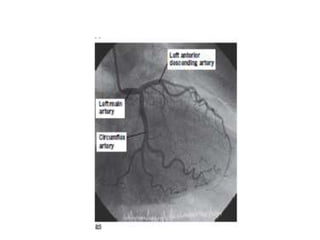

• LEFT HEART CATHETERIZATION:

• Left heart catheterization is usually performed via the right

femoral artery, although the brachial and radial arteries are

sometimes used in patients with significant peripheral vascular

disease.

• A pigtail catheter is advanced up the aorta and manipulated

through the aortic valve into the left ventricle.

• Pressure tracings are taken from the left ventricular cavity.

• The end diastolic pressure is invariably elevated in patients with

left ventricular dysfunction.

• A power injection of radio opaque contrast material is used to

opacify the left ventricular cavity (left ventriculography) and

thereby assesses left ventricular systolic function.

• The catheter is then withdrawn across the aortic valve into

the aorta and the ‘pullback’ gradient across the valve is measured.

• Aortography(a power injection into the aortic root) can be

performed to assess the aortic root and the presence and severity

of aortic regurgitation.